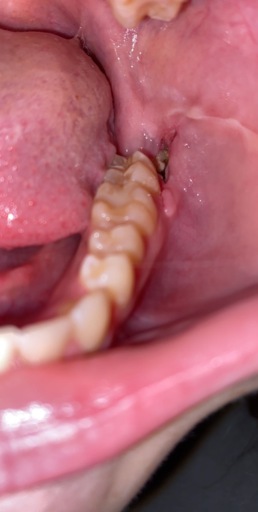

Wisdom Tooth Removal, Infection?

I got my wisdom teeth removed on January 8th (it is now Jan 23) and I'm not sure if I'm healing properly. I am unable to visit my oral surgeon again, as I attend school out of state from where I had the procedure otherwise I would go in for a quick...